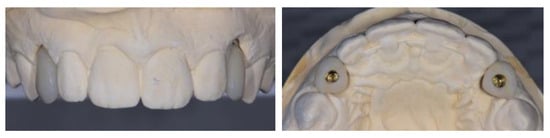

2.5. Individual Cases Description

- Case 1:

- Case 2:

- Case 3:

- Case 4:

- Case 5: